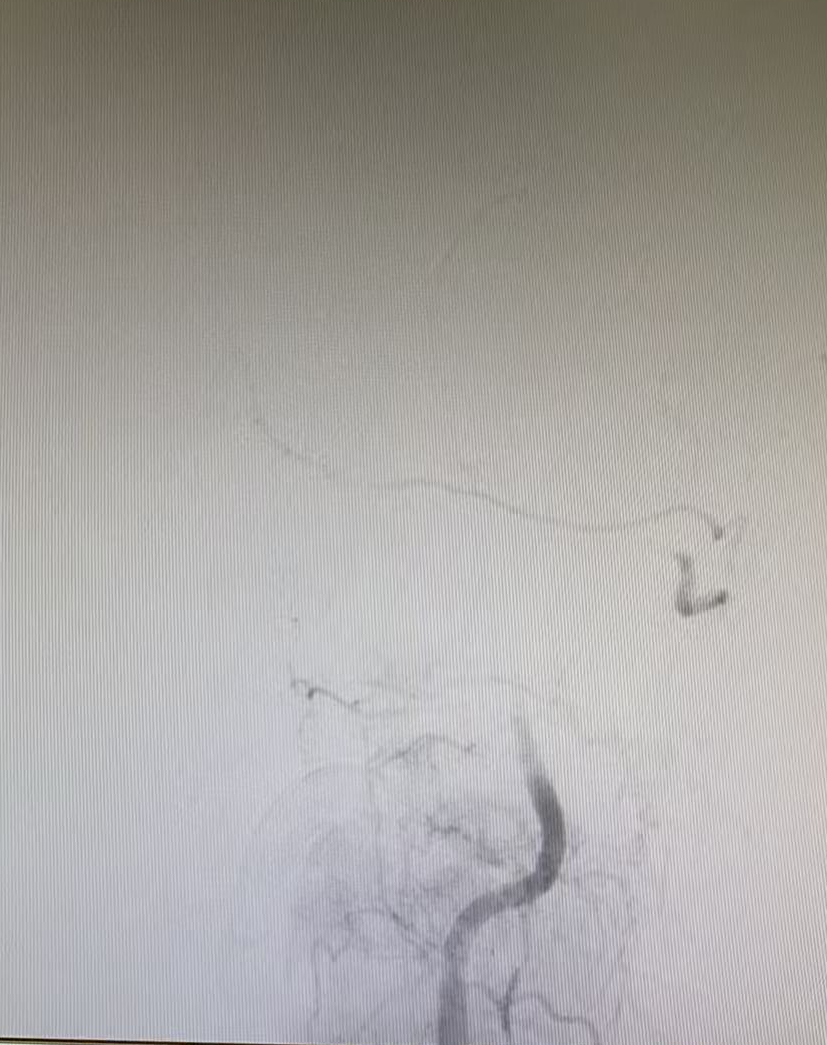

術(shù)前血管閉塞